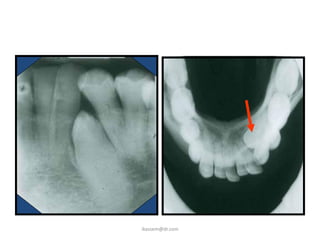

Mandibular Occlusal

Pathology     Sialoliths   Pedo anterior